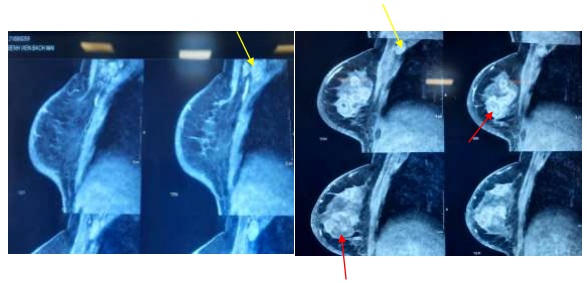

| Hình ảnh cộng hưởng từ vú Tổn thương u vú đa ổ (mũi tên màu đỏ). Hạch nách phải (mũi tên màu vàng). Ảnh: BVCC |

Qua thăm khám, các bác sĩ phát hiện nhiều hạch nách phải chắc kích thước 2 cm, di động kém. Vú phải có tình trạng da nề đỏ trên 1/3 vú, phù da, không loét vú, tụt núm vú, sờ nóng. Vú có 2 u, một u vị trí trung tâm kích thước 5 cm, chắc, dính da, không di động, một u vị trí ¼ dưới ngoài kích thước 2,5 cm, chắc, còn di động, không dính da. Không có nhân vệ tinh. Vú trái cân đối, không sờ thấy khối.

Các xét nghiệm cận lâm sàng công thức máu, sinh hóa máu, X-quang tuyến vú, cộng hưởng từ tuyến vú và kết quả giải phẫu bệnh chẩn đoán xác định bệnh nhân ung thư vú phải thể viêm cT4dN2aM0 (giai đoạn IIIB).